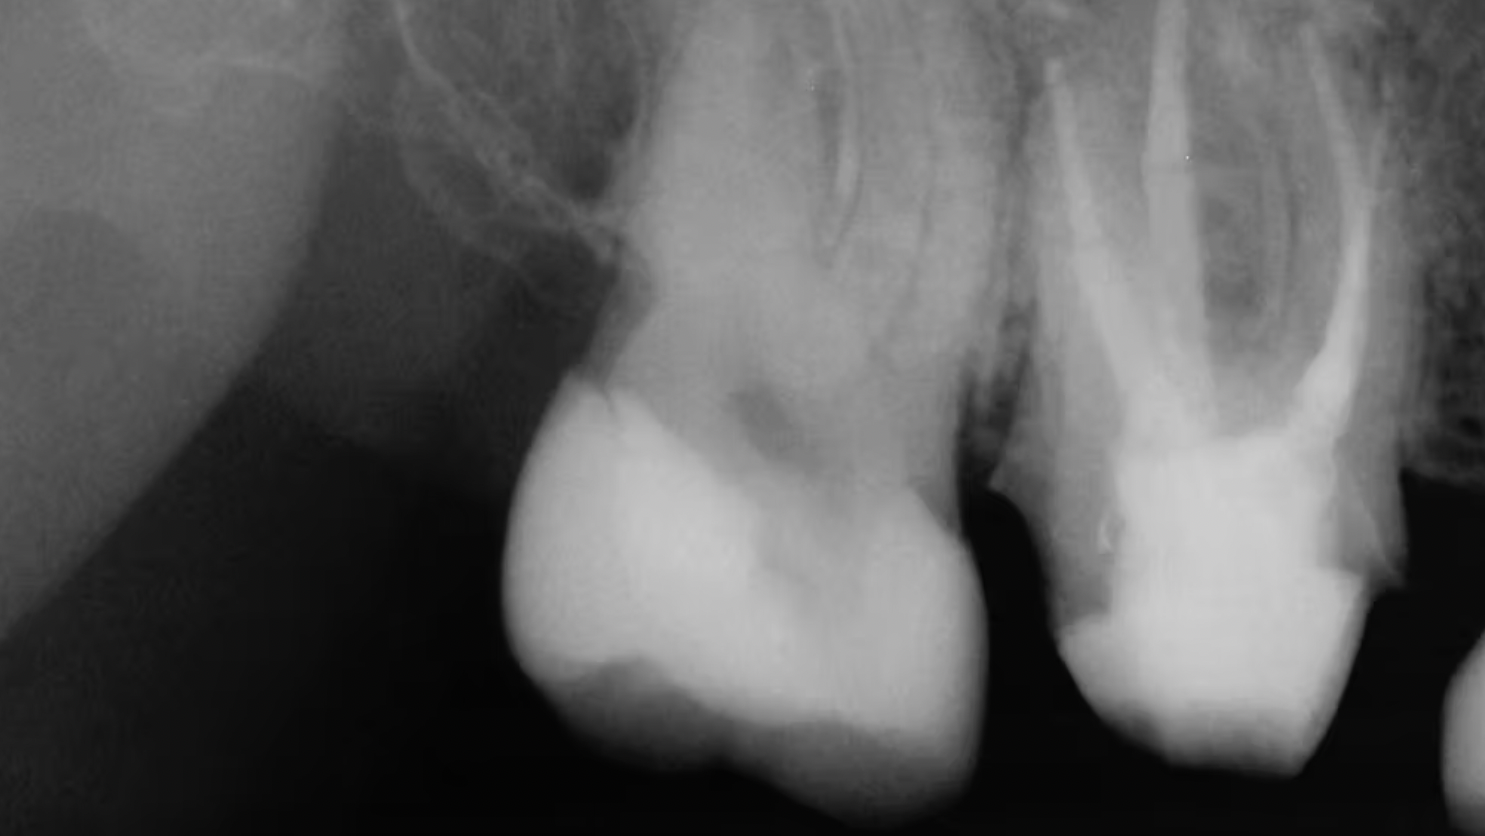

Less than one-half of the coronal tooth structure remaining (Figs. 1-6)

It is my opinion, regardless of the other factors present, that it is still advisable to place a post or posts in such teeth. Endodontically treated teeth with less than one-half of the coronal tooth structure remaining have a reduced chance of long-term service, and patients should be so advised as the treatment plan is developed.